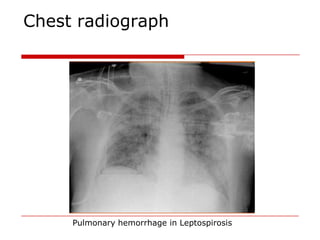

Chest radiograph

 Three radiographic patterns:

1.small nodular densities (50-60%);

2.confluent areas of consolidation (10-20%); and

3.diffuse, ill-defined, ground-glass density (20-

30%).

 Serial radiographs may show a tendency for the

nodular pattern to be followed by confluent

consolidation and/or ground-glass density.

 Abnormalities are bilateral, non-lobar in all

cases, and have a marked tendency toward

peripheral predominance

Pulmonary hemorrhage in Leptospirosis